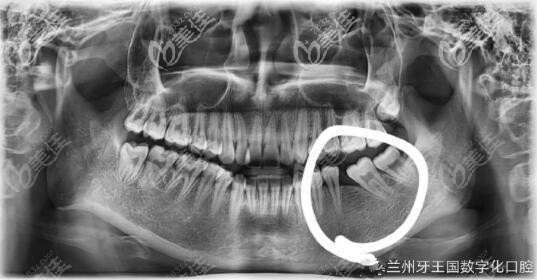

下牙后牙缺失一颗,原本冲着缺牙去医院就诊,想把缺牙种植,避免邻牙受影响。兰州牙王国口腔医生查看后说我下排智齿长得好,去看正畸医生看看能不能把智齿拉往前拉。

其实自己的牙齿也是有些问题,有点咬合太紧,牙王国正畸医生生建议我不进行种植,我的智齿是可以充当磨牙的,这样不用拥有一颗假牙了。